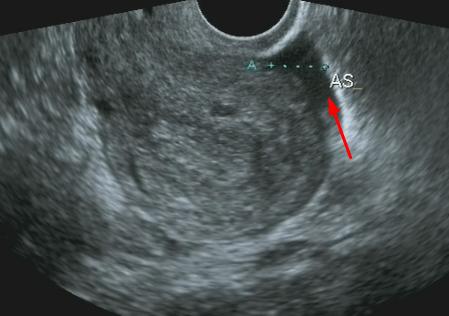

可以的,而且能够测量出深度,大致反应积液的量的情况。

宫外孕破裂,大量积血

黄体破裂,盆腔大量积血